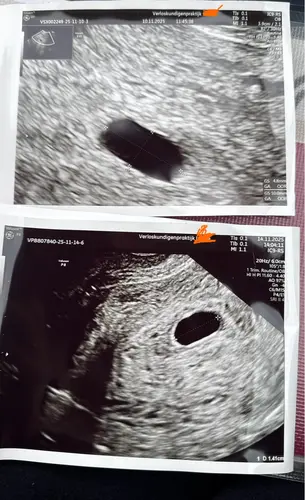

Ik had zelf bij de eerste echo meteen al een slecht gevoel(bleek maar 5w6d te zijn terwijl ik zelf rond de 7w dacht).

Mijn verloskundige schrok van mijn reactie en gaf juist aan dat ze dit vaker zien. Meestal komt het dan gewoon goed maar duurde de innesteling wat langer/was die later of was de ovulatie later dan gedacht.